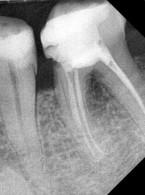

SPECJALISTA RADZI: Nieskuteczna apikotomia wierzchołka korzenia – ponowna resekcja czy powtórne leczenie kanałowe?

Zgłosiła się do mnie 60-letnia pacjentka z nieszczelną i nieestetyczną koroną protetyczną osadzoną na zębie siecznym szczęki. Pacjentka poinformowała, iż ząb był poddany przed laty zabiegowi resekcji. Wykonane zdjęcie potwierdziło wcześniej wykonaną apikotomię oraz obecność niewielkich zmian zapalnych w tkankach okołowierzchołkowych. W kanale stwierdzono dobrze kontrastujący się ćwiek (prawdopodobnie srebrny); w części koronowej kanału był widoczny krótki indywidualny wkład koronowo korzeniowy. Co mogę zasugerować pacjentce? Jakie są możliwości leczenia?